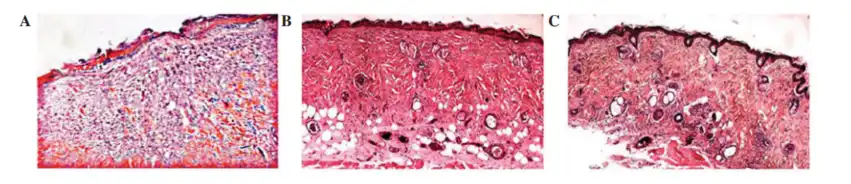

Type I and type III collagen are the main components of the skin dermis, and Centella asiatica extract can promote the synthesis of these two types of collagen, thereby densifying the collagen in the papillary dermis.

A: Untreated skin section; B: 1% Centella asiatica extract aqueous solution (8 days)

2. Promote wound healing

Asiaticoside powder and madecassoside can induce the synthesis of type I collagen in dermal-derived human fibroblasts through the phosphorylation of Smad2 and Smad3, reduce oxidative stress on the wound surface, and thus promote wound healing.

A: Vaseline; B: Asiaticoside; C: Madecassoside (14 days)